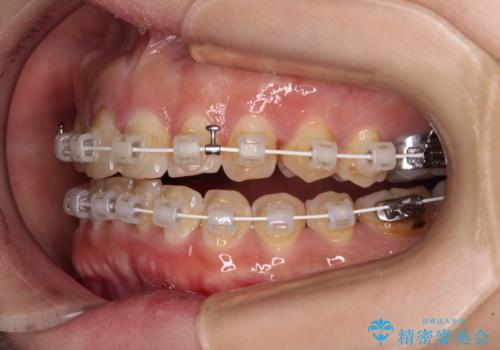

- 飛び出た上の前歯を気にして来院された患者様です。

奥歯の咬み合わせは、上顎歯列が理想的な一よりも数mm前方にある状態でした。

なるべく早めに治療を終えたいとのことで、補助装置を用いて上顎臼歯を後方に移動させ、同時にワイヤー装置にて整えることとしました。

舌の突出癖が原因で上下の歯に大きなスペースが生じていたため、舌のトレーニングをしっかり行っていただくことで、上顎歯列をスムーズに移動させることができました。